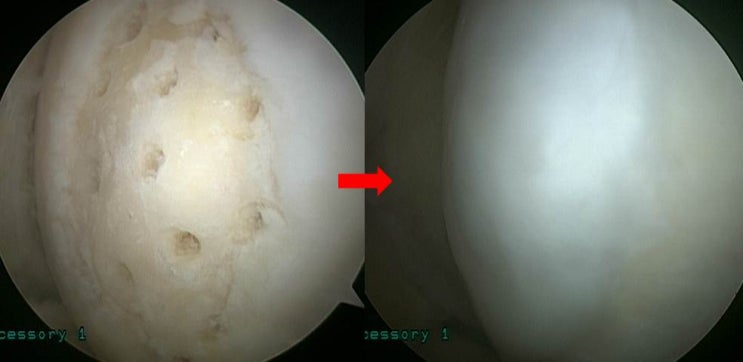

슬개골 탈구 및 슬개연골 손상에서 관절경적 치료 및 슬개연골 고정술의 결과

26세 여자환자로 넘어지면서 발생한 무릎 통증을 주소로 본원으로 내원하였다. 이학적 검사상 fluid collec...